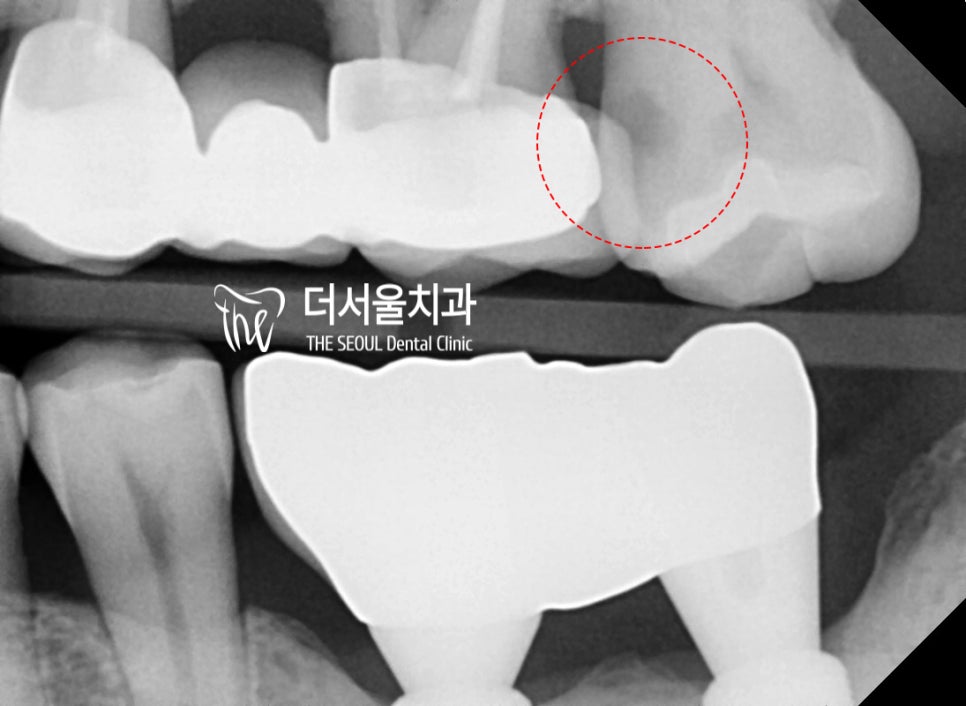

교익 방사선 사진(bite wing)에서도

충치의 위치는 계속 확인이 됩니다.